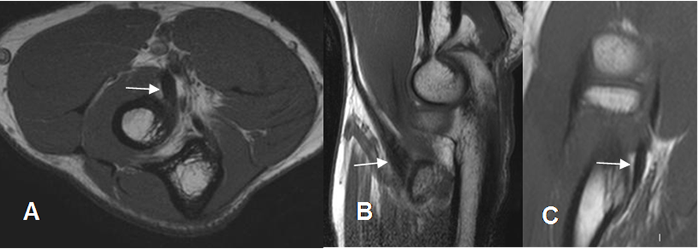

El seudodefecto troclear, tiene similares características y se aprecia hacia el fondo de la cavidad troclear del cúbito. (Fig 9).

Fig 9. Seudodefecto troclear.

A: Rx lateral y B: RM sagital en T1. Irregularidad en la cortical de la cavidad coronoides.

C: RM sagital en STIR. Estudio normal, descartando lesiones óseas.